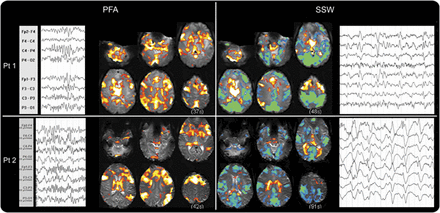

结构异常。

10例(77%),MRI异常(皮质畸形发展(MCD) 5)。这个组织的损伤变化很大程度上考虑到类似癫痫表型。焦发育和创伤性损伤是常见(图1中,得了)。1和3的病人,我们发现明确的结构性损伤,没有发现,一个重要的考虑因素在老年患者被宠坏的gradient-echo成像可能没有被反映在他们的早期,后来制度化和保守的管理。

焦点和边音的放电。

焦简易爆炸装置被记录在2例(4和11如图依照病人)。两个独立的焦点是记录在病人4(一左一右)。局部放电与皮质激活相关的整合与简易爆炸装置。

前两个病人、胼胝体(病人4和11,图4)。在这些患者中,PFA排放不定地显示正确,或者发出强调。这些边音的PFA排放相应产生的单侧性的招聘网络上面描述。